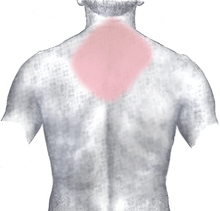

Myocardial infarction (MI) or acute myocardial infarction (AMI), commonly known as a heart attack, occurs when blood flow stops to a part of the heart causing damage to the heart muscle. The most common symptom is chest pain or discomfort which may travel into the shoulder, arm, back, neck, or jaw. Often it is in the center or left side of the chest and lasts for more than a few minutes. The discomfort may occasionally feel like heartburn. Other symptoms may include shortness of breath, nausea, feeling faint, a cold sweat, or feeling tired.[1] About 30% of people have atypical symptoms,[2] with women more likely than men to present atypically.[3] Among those over 75 years old, about 5% have had an MI with little or no history of symptoms.[4] An MI may cause heart failure, an irregular heartbeat, or cardiac arrest.[5][6]

The onset of symptoms in myocardial infarction (MI) is usually gradual, over several minutes, and rarely instantaneous.[18] Chest pain is the most common symptom of acute MI and is often described as a sensation of tightness, pressure, or squeezing. Chest pain due to ischemia (a lack of blood and hence oxygen supply) of the heart muscle is termed angina pectoris. Pain radiates most often to the left arm, but may also radiate to the lower jaw, neck, right arm, back, and upper abdomen,[19] where it may mimic heartburn. Levine's sign, in which a person localizes the chest pain by clenching their fists over their sternum, has classically been thought to be predictive of cardiac chest pain, although a prospective observational study showed it had a poor positive predictive value.[20]

Atypical symptoms are more frequently reported by women, the elderly, and those with diabetes when compared to their male and younger counterparts.[23][24] Women also report more numerous symptoms compared with men (2.6 on average vs. 1.8 symptoms in men).[23] The most common symptoms of MI in women include dyspnea, weakness, and fatigue. Fatigue, sleep disturbances, and dyspnea have been reported as frequently occurring symptoms that may manifest as long as one month before the actual clinically manifested ischemic event. In women, chest pain may be less predictive of coronary ischemia than in men.[25] Women may also experience back or jaw pain during an episode.[26]